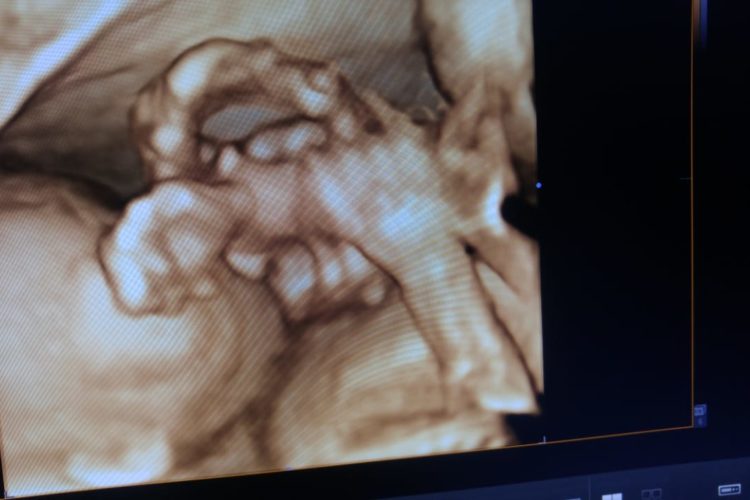

4D ANOMALY SCAN

5D SONOGRAPHY